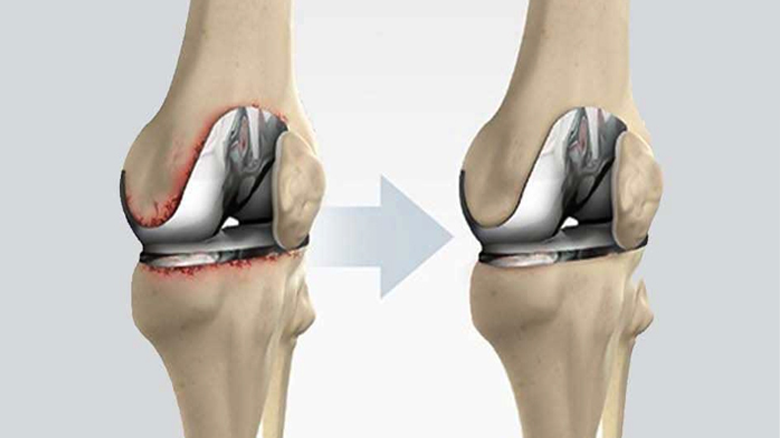

Total Knee Replacement (TKR)

We provide Total Knee Replacement (TKR) using modern implants and less invasive surgical techniques, aimed at reducing recovery time and improving long-term comfort.

Best For:

- Severe knee pain

- Advanced arthritis